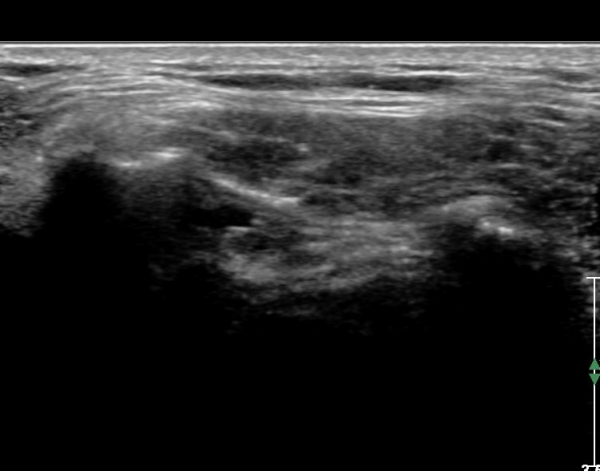

ŽÃËÀÚ¸¦ Á»´õ ¸»´ÜÀ¸·Î À̵¿ ÈÄ(¶Ç´Â ¾Æ·¡·Î ±â¿ïÀÎ ÈÄ) ³»ÃøºÎ¸¦ Á¶ÀýÇÏ´Ï °ß°©ÇÏ±Ù°Ç Ç¥ÃþÀ¸·Î Á¡¾×³¶³» ¼ö¾×Àú·ù°¡ °üÂûµÈ´Ù(»çÁö 3, 4). ŽÃËÀÚ¸¦ Á¶Á¤ÇÏ´Ï ÀÌµÎ¹Ú°Ç ÁÖÀ§ ¼ö¾× Àú·ù¿Í Á¡¾×³¶³» ¼ö¾×Àú·ù°¡ °üÂûµÇ¾î Á¡¾×³¶¿°°ú Ȱ¾×¸·¿°ÀÌ ÀÖÀ½À» ¾Ë ¼ö ÀÖ´Ù(»çÁø 5).

ŽÃËÀÚ¸¦ ¾à°£ ¿ÜÃøÀ¸·Î À̵¿ÇÏ¿© Á¶ÀýÇÏ´Ï À̵ιڰÇÀÌ °üÂûµÇ°í(»çÁø 6) ¾à°£ ¸»´ÜÀ¸·Î À̵¿ÇÏ´Ï °ÇÁÖÀ§ ¼ö¾×Àú·ù°¡ °üÂûµÈ´Ù(»çÁø 7). Á߸³À§¿¡¼ ŽÃËÀÚ¸¦ ¾î±ú ¿ÜÃø¿¡ ´ë°í °ßºÀ°ú ´ë°áÀýÀÌ ¸ðµÎ º¸À̵µ·Ï Á¶ÀýÇÏ¿© ¿ÜÀüÇÏ¸é¼ Ãæµ¹ ¿©ºÎ¸¦ °üÂûÇÑ´Ù. Á¤Áö »óÅ¿¡¼ ´ë°áÀýÀÇ °ñ °á¼ÕÀÌ °üÂûµÇ¾î ¸¸¼ºÀûÀÎ Ãæµ¹À» ½Ã»çÇÑ´Ù(»çÁø 8). ¿ÜÀü½Ã »ó¿Í°ñµÎ°¡ »ó¹æÀ¸·Î ¿òÁ÷ÀÌ°í °ßºÀ°ú Ãæµ¹ÇÔÀÌ °üÂûµÈ´Ù(»çÁø 8, ÷ºÎµ¿¿µ»ó 1).